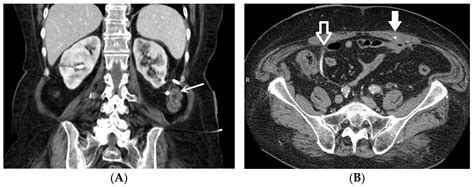

The stent is typically made of medical-grade plastic or silicone, designed to be biocompatible, meaning it can safely remain inside the body for a specific period. It features small curls at both ends—one sitting in the kidney and the other in the bladder—which act as anchors to keep the device from moving out of place. This design is why they are often called "double-J" or "pig-tail" stents.

• Kidney Stones: These are the most frequent cause. A stone may become stuck in the ureter, causing a blockage and intense pain.

• Tumors or Growths: External pressure from a tumor in the pelvis or abdomen can compress the ureter.

4. Stent Placement: The stent is threaded over the guidewire and moved into the correct position. Once verified using X-ray imaging (fluoroscopy), the guidewire is removed, leaving the stent in place.